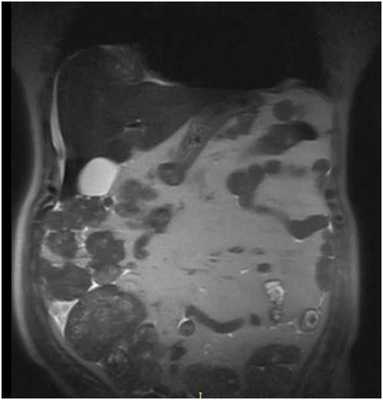

![МРТ брюшной полости]()

МРТ брюшной полости. На МР-томограмме в корональной плоскости отмечаются МР-признаки метастатического поражения брюшины в виде неправильно округлой формы узловых патологических образований (серый МР-сигнал на представленном изображении).